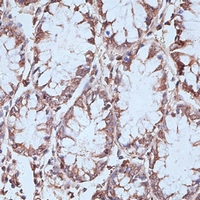

Immunohistochemical analysis of NFE2L1 staining in human colon formalin fixed paraffin embedded tissue section. The section was pre-treated using heat mediated antigen retrieval with sodium citrate buffer (pH 6.0). The section was then incubated with the antibody at room temperature and detected using an HRP conjugated compact polymer system. DAB was used as the chromogen. The section was then counterstained with haematoxylin and mounted with DPX. -